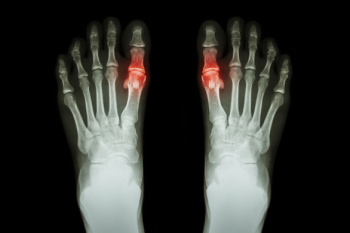

Gout is a form of arthritis that is characterized by sudden, severe attacks of pain, redness, and tenderness in the joints. The condition usually affects the joint at the base of the big toe. A gout attack can occur at any random time, such as the middle of the night while you are asleep.

- Intense Joint Pain – Usually around the large joint of your big toe, and it most severe within the first four to twelve hours

- Inflammation and Redness -Affected joints may become swollen, tender, warm and red